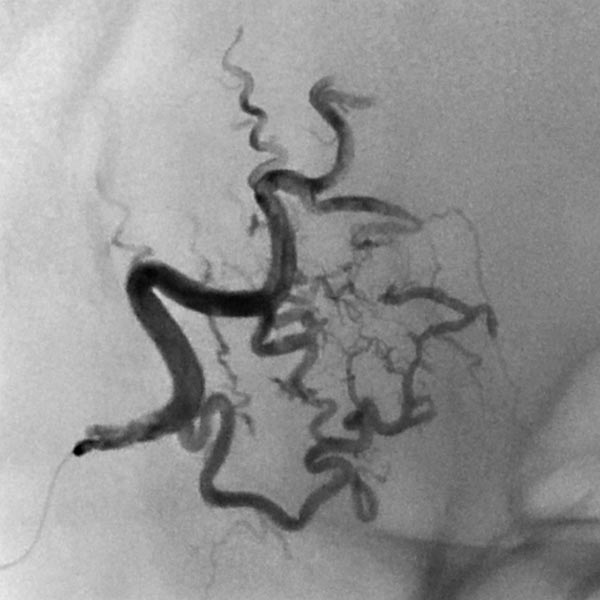

Die digitale Subtraktionsangiographie (DSA) über rechte die Arteria carotis externa und die Arteria temporalis superficialis zeigt eine feinfistulöse AVM mit deutlich dilatierten Feederarterien an der rechten Stirn und sofortigem venösen Abstrom.

Der Mikrokatheter wurde bis direkt zum Nidus vorgebracht. Nach Darstellung des Nidus sofortiger, direkter venöser Abstrom (DSA, venöse Phase) aus der Läsion über dilatierte Venen. Dies sichert die Diagnose einer AVM.